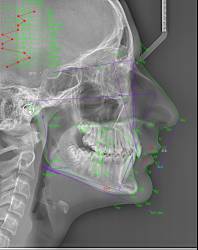

Телерентгенография (Цефалометрия)

-Телерентгенография с ортодонтски анализ